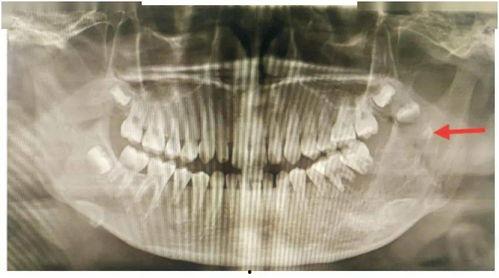

其实,拔牙手术虽然看似简单,但其中却隐藏着不少风险。据相关数据显示,每年因拔牙手术意外死亡的案例并不在少数。那么,拔牙手术究竟有哪些风险呢?

医生在拔牙手术过程中,如果操作不当,可能会损伤神经、血管等重要组织,引发并发症。